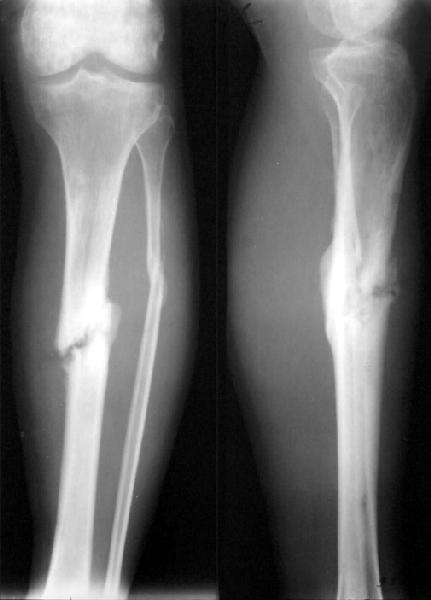

Пациент 26 лет 7.02.2002 был сбит легковой машиной в небольшом городке. По поводу перелома костей голени 15.02.02 в местной больнице был наложен аппарат, который был снят 25.05.02. Перелом закрытый, воспаления таней у спиц, со слов больного, не было. После снятия была патологическая полдвижность, наложена гипсовая шина, которую пациент через месяц снял сам. Ходил с частичной нагрузкой. Сейчас ходит с тростью, отмечает болезненность в проекции перелома. Явной патологической подвижности при осмотре не выявили, хотя, конечно, нагрузки прикладывали не самые максимальные. Снимки свежие (фас+профиль и косые).Какой здесь на сегодня уместен диагноз? Псевдартроз? Несросшийся перелом? Замедленная консолидация? Сросшийся на органиченном участке?Как-то иначе? В плане у нас - закрыто заштифтовать большеберцовую кость "как есть" с динамическим блокированием. Или потребуется закрытая остеоклазия? Надо ли делать остеотомию малоберцовой? Нужны ли, на Ваш взгляд, еще какие-то дополнительные меры, костная пластика, например?Заранее спасибо.

Regarding case of 26 yo patient with tibia shaft fracture that has gross motion 8 months after XF and casting.

Diagnosis? IMHO this is a delayed union with impending nonunion.

The time difference between delayed union and nonunion varies; sometimes referred to as 1 year, 9 months or 6 months; sometimes twice the normal healing time ( 2 x 16 weeks for tibia shaft); sometimes other considerations.